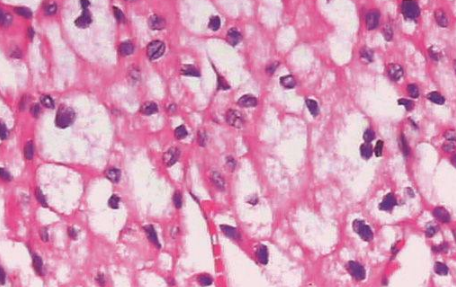

肾嫌色细胞癌是一种非常见的肾细胞恶性肿瘤,但与普通的肾细胞恶性肿瘤相比,它的恶性程度相对较低,它的形态比较特殊,恶性程度不高,根据临床医学认识,它起源于肾集合管上皮,目前在治疗此类恶性肿瘤时,大多会进行根治性切除。

全肾脏切除后往往预后效果好,与同期其他类型的恶性肿瘤相比,它的5年生存期比例相对较大。